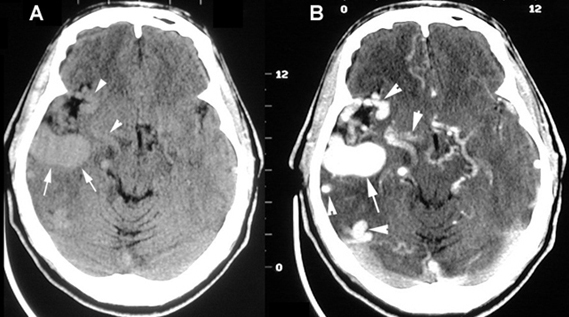

Arterial Venous Malformation

- A: Non-contrast CT shows a lobular mass in the right hemisphere. The arrowheads in A point to nonenhanced vessels.

- B: Post-contrast demonstrates intense enhancement of the mass with multiple prominent vascular channels (arrowheads) - large AVM.